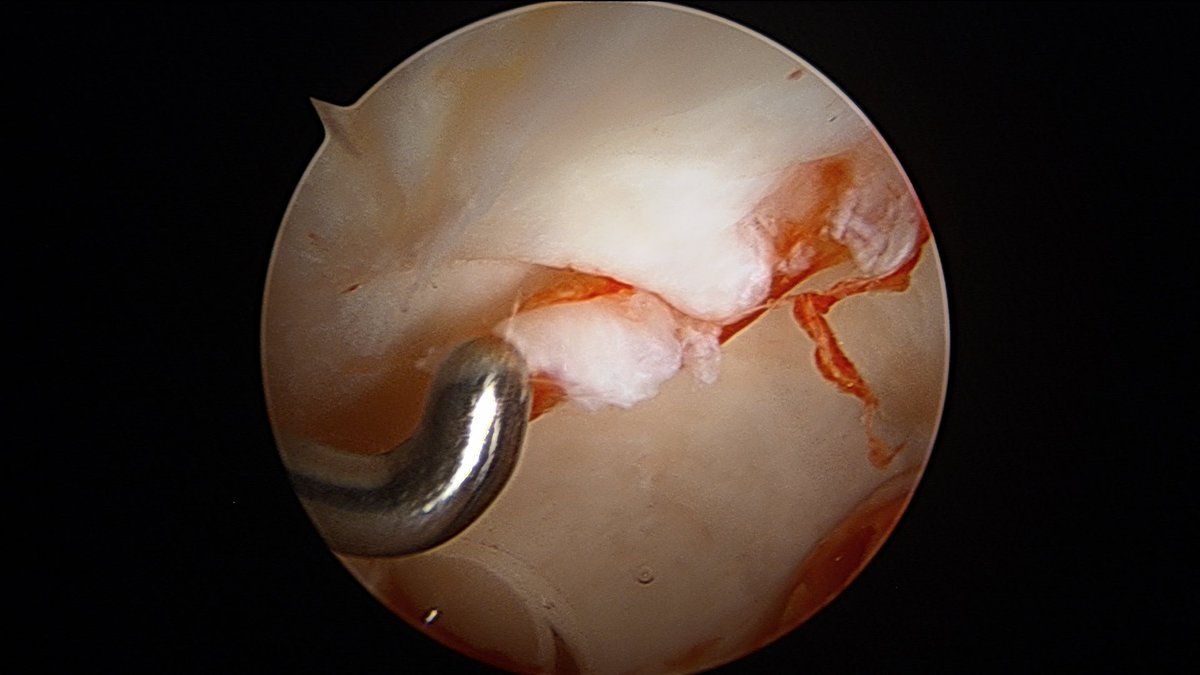

So, if a patient has a labral tear like this...

For this labral tear, optimal results occur when addressing the labral tear and addressing the cause of the damage. #HipArthroscopy pic showing repaired labral. X-ray showing surgical correction of #HipFAI.